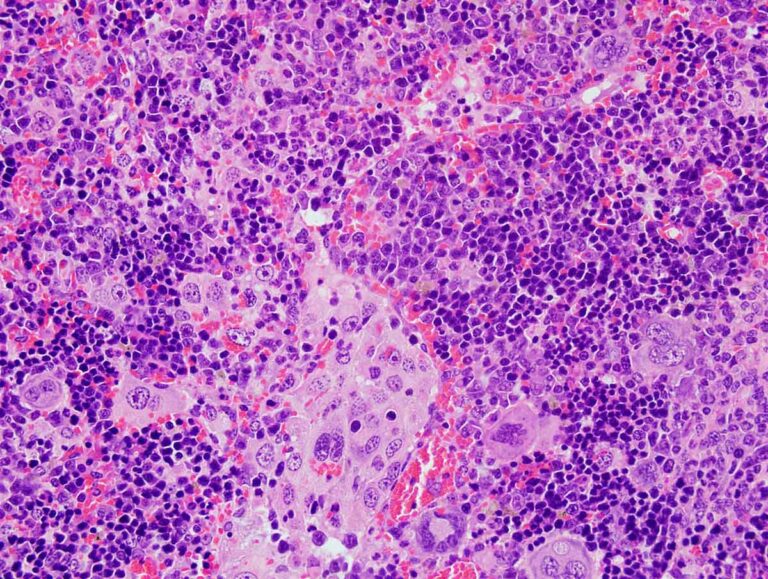

El descubrimiento permitirá identificar fármacos aptos para tratar el linfoma periférico de células T y probar su eficacia en fase...